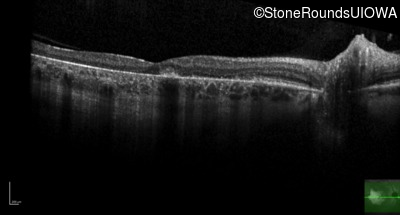

Age at visit: 43 years

Macular Disease WDR19 His344Arg CAT>CGT Ser485Ile AGT>ATT AR